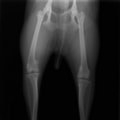

■ 症例24 キャバリア 7か月

左右膝蓋骨内方脱臼(左:グレードⅣ 右:グレードⅢ)

以前から左右後肢の跛行が認められ、整形外科学的検査・レントゲン検査により左右の膝蓋骨脱臼が認められた。症状が重度である左膝の膝蓋骨脱臼整復術を行った。外科手技は縫工筋及び内側広筋の解放、脛骨粗面の外側転位、滑車ブロック形造溝術、内外側関節方の縫縮を実施した。術後一か月時点で、左の膝蓋骨は安定しており経過は良好である。

本症例は成長期における重度の膝蓋骨脱臼であり、術後の再発の可能性もあるため、経過をしっかりと観察していく必要がある。また、今回手術を実施していない右膝に関しても経過を観察し、手術を検討していくこととする。